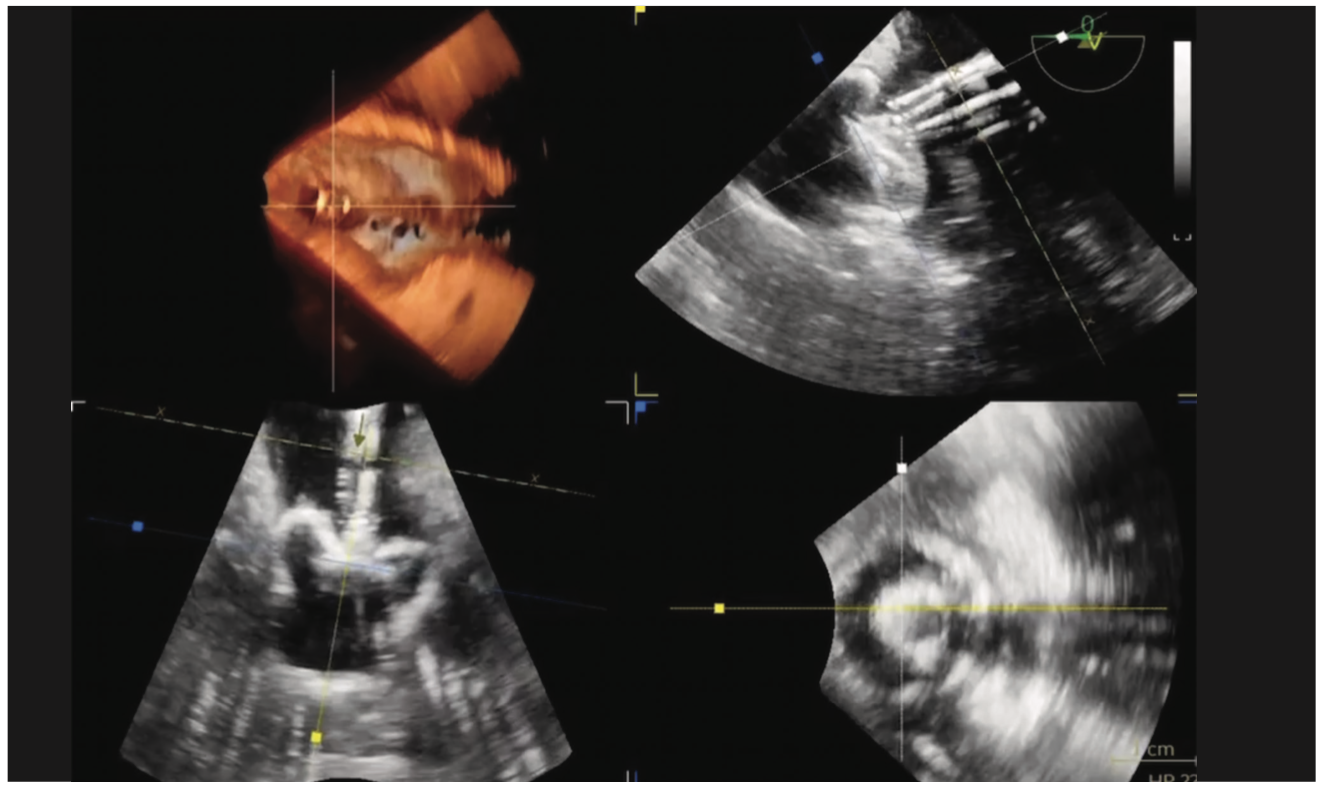

The Watchman is a parachute-shaped device made out of a nitinol cage with a polyethylene terephthalate fabric membrane cap. The original Watchman 2.5 device had an open design with a single row of 10 active fixation anchors, while the newly designed Watchman FLX device has a closed design with a dual row of 18 fixation anchors (Figure 1A). The Watchman FLX comes in 5 sizes, which are selected based on depth and ostial sizes of the LAA (Figure 1B).

In this section, we will provide an overview of our periprocedural process and experience with the Amulet occluder at Ascension Providence. The Amulet occluder received US Food and Drug Administration approval based on the Amulet IDE trial.3,4 The Amulet occluder is a double-disc device consisting of a nitinol mesh with polyester fabric cover. Unique to the device is the dual-seal function using the lobe component placed at the LAA ostium and the disc positioned at the orifice. A single row of fixation anchors are positioned circumferentially around the distal lobe. There is a range of sizes available in lobe length (diameter range 16-34 mm), with concomitant gradation in lobe length and disc sizes (Figure 3).